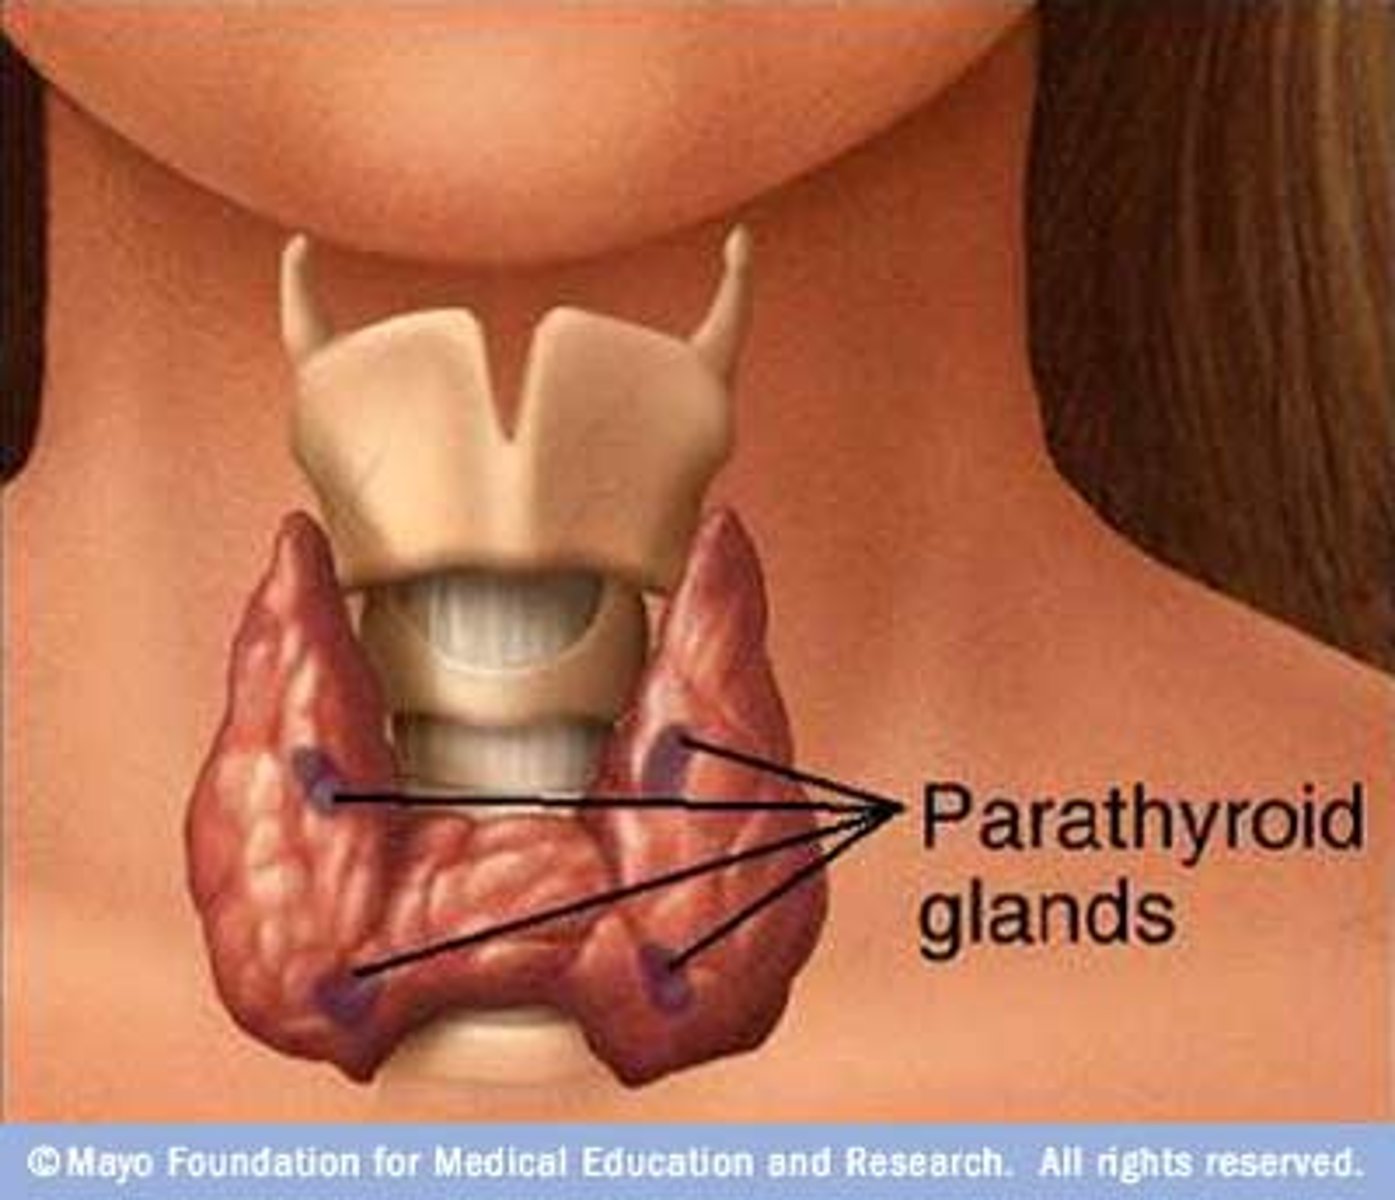

Parathyroid

in the neck next to thyroid gland

parathyroid hormone

PTH (parathyroid hormone)